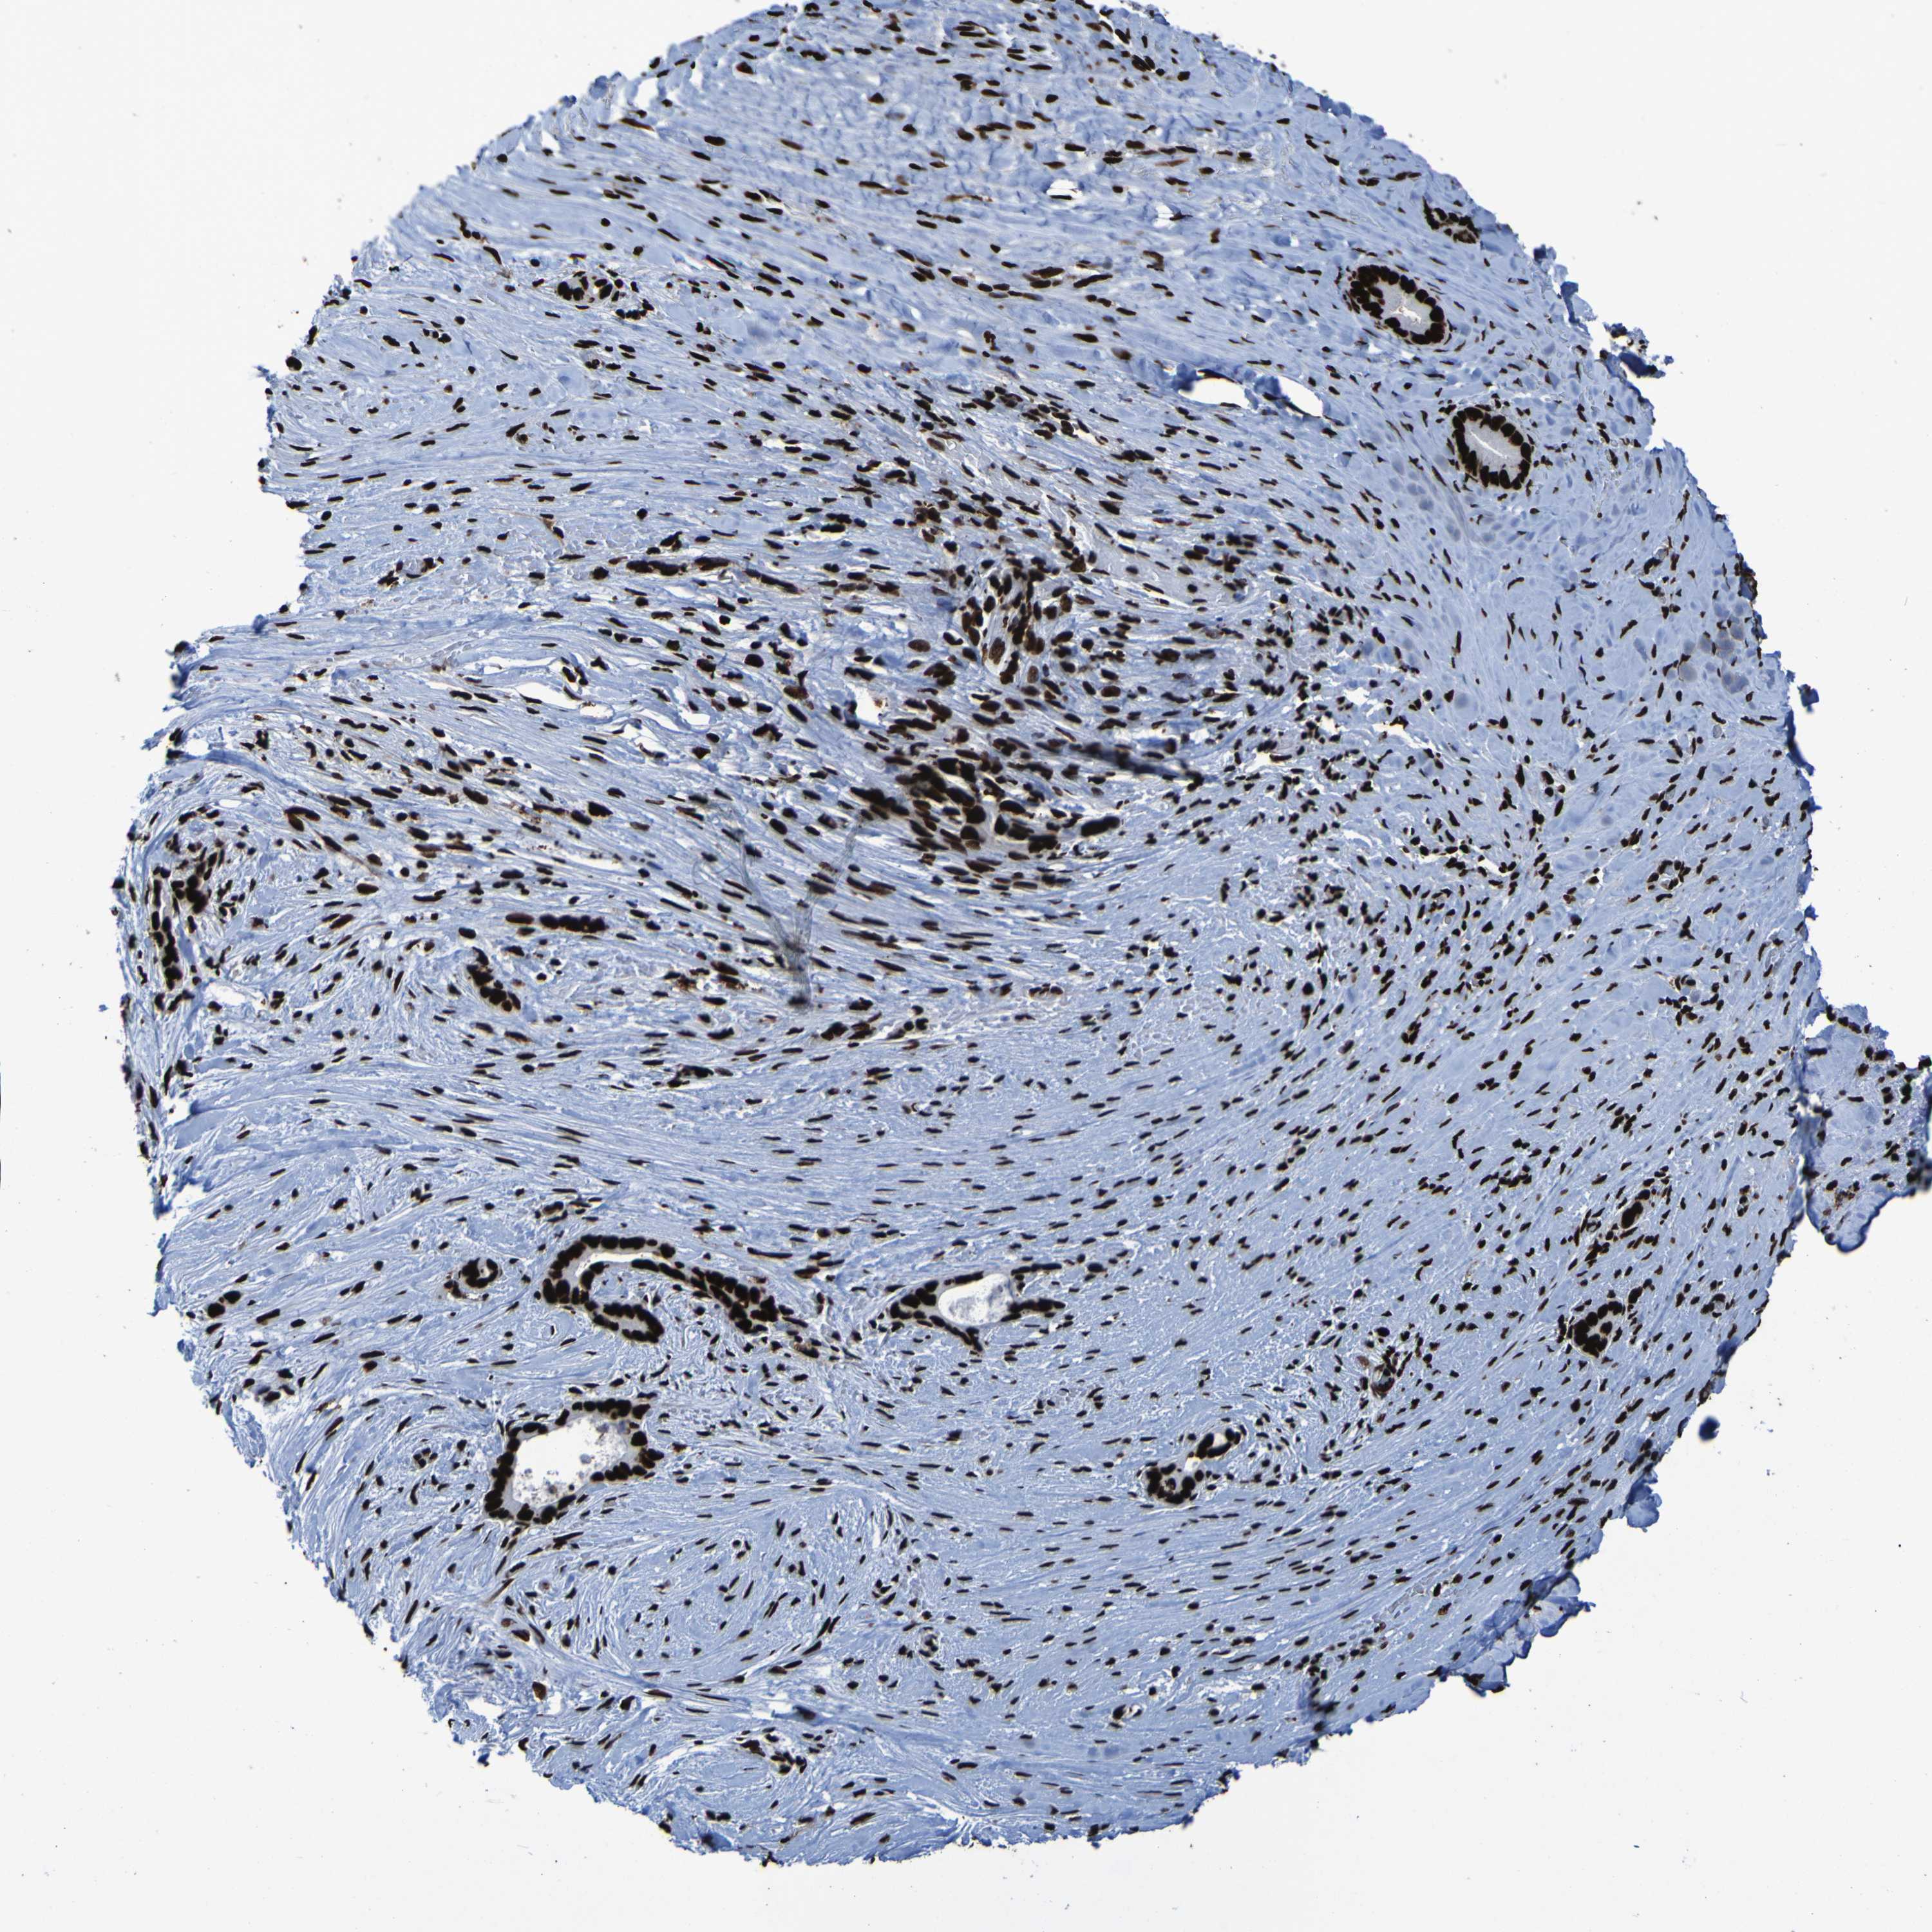

LIVER CANCER - Protein expressioni

A mouse-over function shows sample information and annotation data. Click on an image to view it in a full screen mode. Samples can be filtered based on level of antibody staining by selecting one or several of the following categories: high, medium, low and not detected. The assay and annotation is described here.

Antibody stainingi

Antibody staining in the annotated cell types in the current human tissue is reported as not detected, low, medium, or high, based on conventional immunohistochemistry profiling in selected tissues. This score is based on the combination of the staining intensity and fraction of stained cells.

Each image is clickable and will lead to virtual microscopy that enables deeper exploration of all samples and also displays staining intensity scores, fraction scores and subcellular localization as well as patient and tissue information for each sample.

Antibody HPA011384

Antibody CAB012983

Staining

High

Medium

Low

Not detected

Intensity

Strong

Moderate

Weak

Negative

Quantity

>75%

75%-25%

<25%

None

Location

Nuclear

Cytoplasmic/membranous

Cytoplasmic/membranous,nuclear

Cholangiocarcinoma

Carcinoma, Hepatocellular, NOS